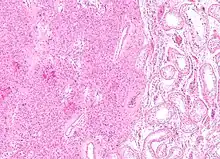

Micrograph of a granulosa cell tumour, a type of sex-cord–gonadal stromal tumour. H&E stain.